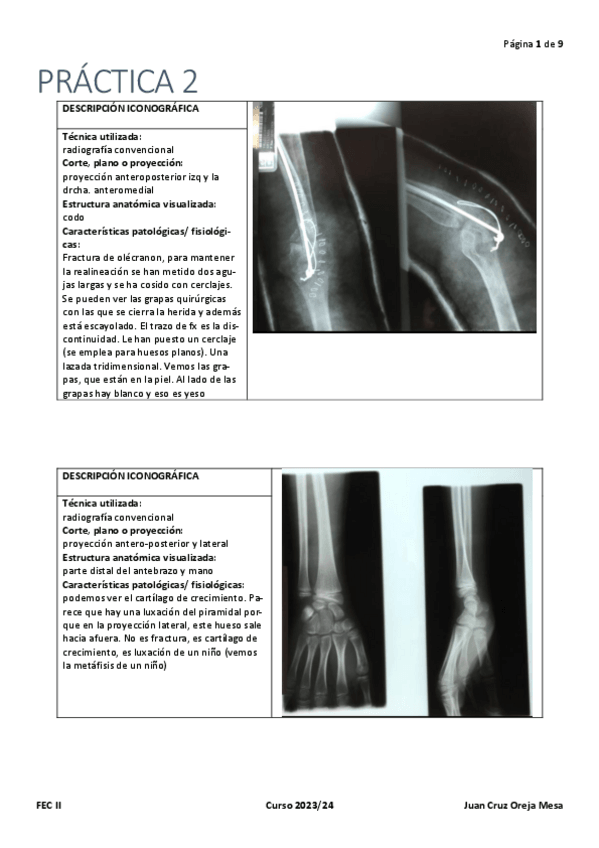

PRACTICA-1.-RADIODIAGNOSTICO.pdf

PRACTICA-2.-RADIODIAGNOSTICO.pdf

PRACTICA-3.-RADIODIAGNOSTICO.pdf